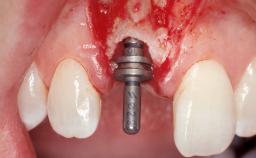

Immediate Flapless Placement of an Implant in a Maxillary Right Lateral Incisor Site

This 43-year-old male patient, a non-smoker, came to our practice because of a fracture of tooth 12 caused by a bicycle accident. Due to the combined para- and infrabony crown and root fracture, tooth extraction, and subsequent implant placement were suggested to the patient as the therapy of choice. The patient had high esthetic expectations with regard to the treatment outcome and asked for an immediate fixed provisional restoration. His individual esthetic risk profile summed up to a medium esthetic risk.

| Placement Protocol | Immediate implant placement |

| Tooth Site | Maxillary incisor or canine |

| Socket Morphology | Single-root socket |

| Socket Integrity | Sufficient, with intact bone walls |

| Bone Volume | Sufficient, with intact walls |